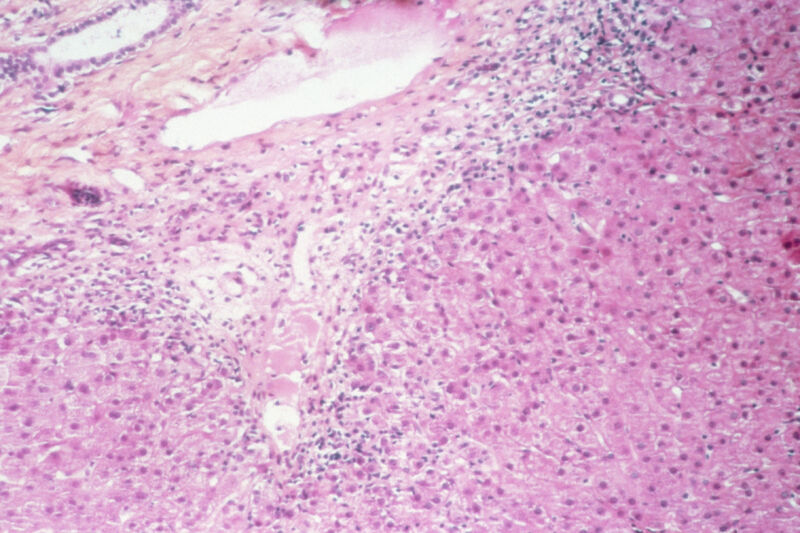

Although the global case count may seem low, severe liver inflammation (aka hepatitis) is uncommon in young children. Health officials in Scotland—who first sounded the alarm over the unexplained cases—realized something was amiss when they saw 13 cases of severe hepatitis in children just in March and April. Usually, Scotland records fewer than four such cases over an entire year.

Health experts around the world are working to understand what’s causing the severe liver injuries. Affected children have consistently tested negative for viruses that attack the liver, namely hepatitis viruses A, B, C, D, and E. So far, there’s no clear link between the cases, nor an association with travel, or a clear connection to an environmental, drug, or food exposure. The vast majority of the cases had not received COVID-19 vaccines, ruling out that possibility.